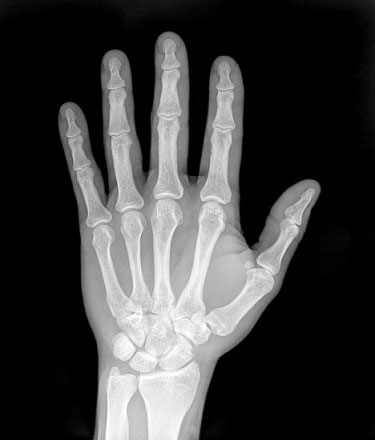

۸- بدن نوزاد انسان تعداد ۶۰ استخوان بیشتر از یک فرد بالغ دارد

نوزاد انسان در بدو تولد با ۳۰۵ استخوان به دنیا میآید که در مقایسه با یک انسان بالغ تعداد آن زیاد میباشد. به تدریج و به همراه رشد، این استخوانها به هم متصل میشوند تا استخوان واحدی را تشکیل دهند. اسکلت نوزاد عمدتاً از غضروف ساخته شده است. همین که شروع به رشد میکند، طی فرایند استخوان سازی، بسیاری از این غضروفها تبدیل به استخوان میشوند. هنگام بلوغ، تعداد استخوانها برابر ۲۰۶ عدد میباشد.